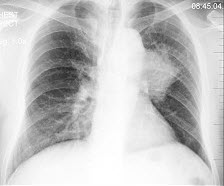

34、单项选择题

早产儿,男,生后12小时,生后8小时出现呼吸困难,如图,最可能的诊断为()

A.新生儿肺炎

B.新生儿湿肺

C.新生儿肺出血

D.新生儿特发性呼吸窘迫综合症

E.胎粪吸入综合征